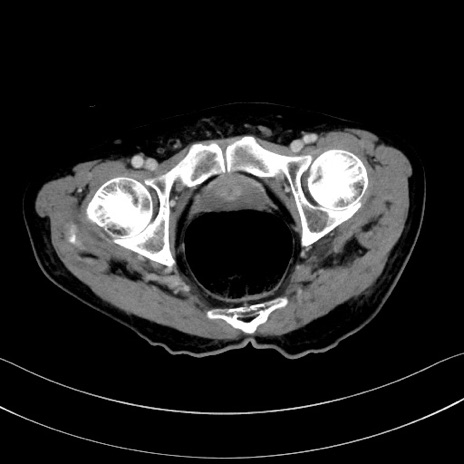

症例28(横断像)

【症例】60歳代男性

【主訴】嘔吐

【現病歴】胃癌にて胃全摘後。食思不振が悪化し、夜中に嘔吐することがある。

【既往歴】胃癌、胃全摘、脾摘、胆摘後

【データ】WBC 5900、CRP 10.56